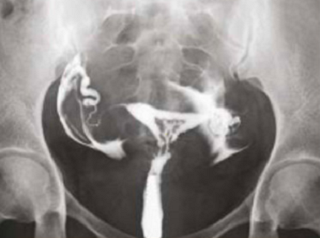

What does HSG assess?

Shape of the uterus

Normal shape

Unicornuate uterus

Complete septate uterus

Patency of fallopian tubes

Open tube

Closed tube

Uterine cavity

Clear/Normal

Submucosal fibroid

Adhesions/Synechiae